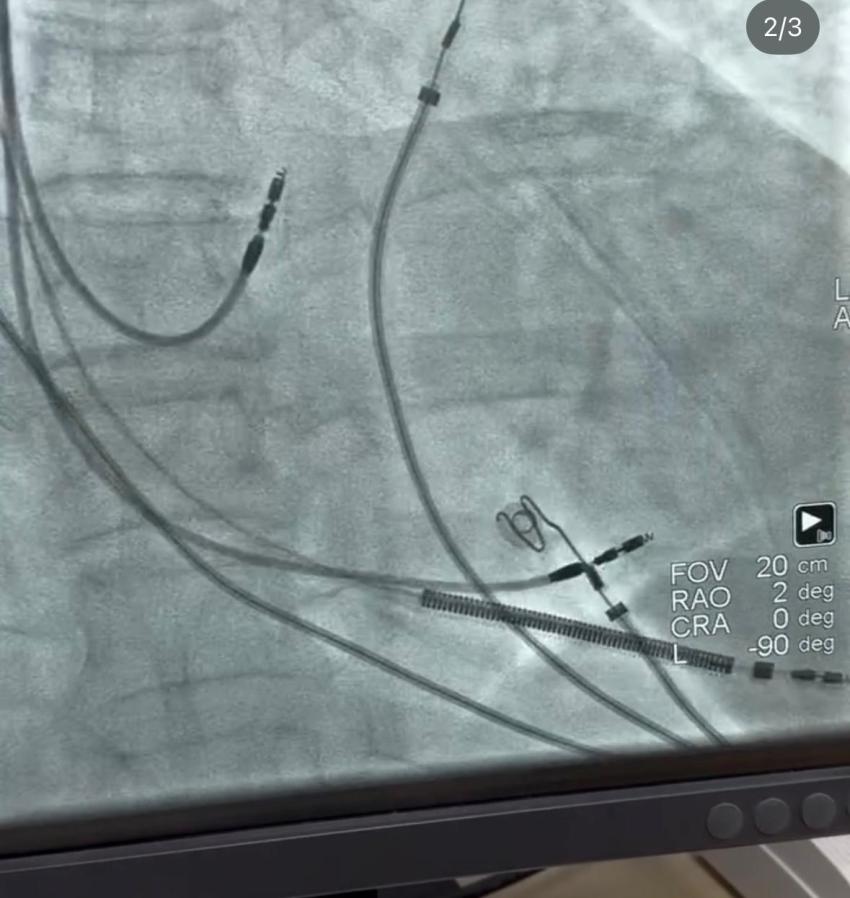

Geleneksel kalp pillerinde, elektrik uyarıları genellikle sağ karıncık bölgesine veriliyor. Bu yöntem kalbin atmasını sağlasa da, uzun vadede kalbin doğal ritminden sapmalar ve bazı olumsuz etkiler görülebiliyor. “Left Bundle Area Pacing” (LBAP) adı verilen yeni yöntem ise, kalbin elektriksel sistemine daha yakın bir noktadan uyarı vererek, kalbin kendi doğal ritmine çok daha yakın atmasını sağlıyor.

“Geleneksel kalp pillerinde kalp kası bazen düzensiz kasılabiliyor, bu da uzun vadede kalp yetmezliğine yol açabiliyor. Sol dal demeti alanı pili ise, kalbin elektriksel sistemine doğrudan müdahale ederek kalbin kendi doğal ileti yollarını kullanıyor. Yani kalbi adeta kendi doğasında, olması gerektiği gibi çalıştırıyoruz.”